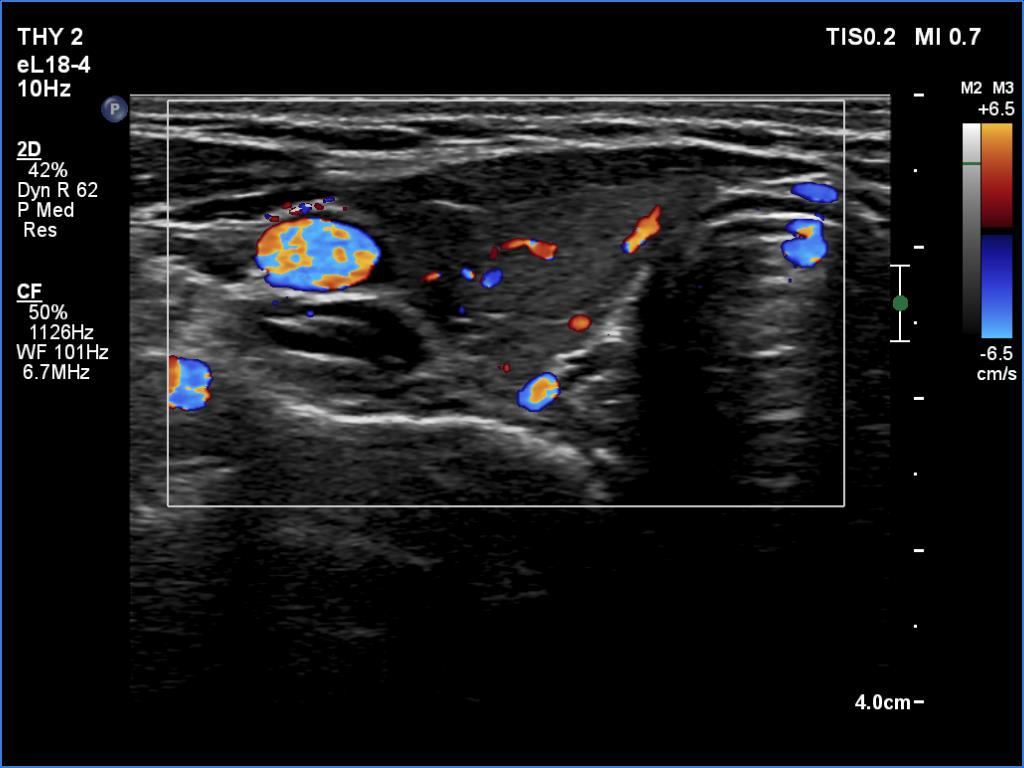

Lymphocytic thyroiditis - case 512 (ultrasonographic picture 3)

Right lobe, transverse view, color Doppler mode. According to the the small, deeply hypoechoic areas, Doppler mode discloses vascularization.